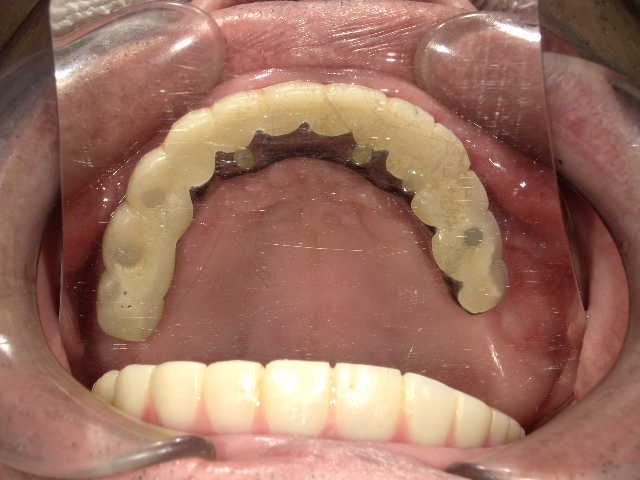

冨田先生についてCASE01 All on 4

下の歯は4本、上の歯は5本インプラントを埋め込み、上下ともに1日で歯をセットしました。上の歯に関しては、単に5本埋入すればいいという問題ではありません。

- コメント

下の歯は4本、上の歯は5本インプラントを埋め込み、上下ともに1日で歯をセットしました。上の歯に関しては、単に5本埋入すればいいという問題ではありません。鼻の下の硬い骨を使ったり、ガミースマイル(=歯茎が見えてしまう笑顔)改善のために骨を削ったりする必要があります。また、下の歯は神経麻痺を回避するためにオトガイ孔(下の神経の出口)にプローブ(=先端の細い専用の器具)を挿入したりと細かなケアが大切です。

また、歯の治療をしてもどうしても歯を残すことが難しい状態に対しても、インプラントを埋めこむと同時に抜歯をすることで、All on 4の治療が可能になります。手術をしたその日のうちに仮歯が入るため、すぐに固定式の歯が必要だというような人にも向いている治療法です。